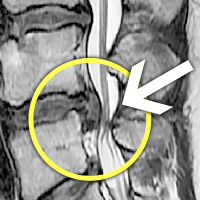

MRI

㸮 , Ͽ Ͽϴ.

㸮 , , ٷ Ͽ Ͽϴ.